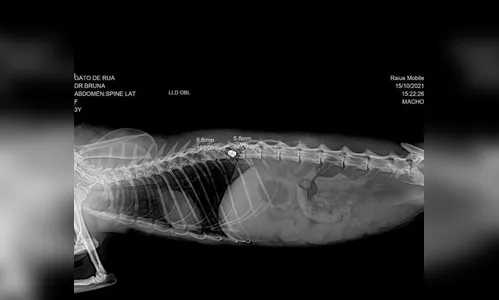

Autor Raio-x indicou a presença de uma bala de arma de fogo na coluna do gato - Foto: Arquivo pessoal

Um gato que está com uma bala de arma de fogo calibre 22 alojada na coluna foi resgatado em Pitangueiras, município vizinho de Astorga. O animal foi encontrado na última quinta-feira (14), na Avenida Sete de Setembro, deitado próximo a um bueiro, e precisa passar por uma cirurgia para extração do projétil.

Após recolher o animal na quinta-feira, Ellen levou para uma clínica veterinária em Astorga. O gato ficou internado tomando soro e medicação para dor. O resultado do exame de raio-x saiu na sexta-feira, 15, indicando paraplegia por conta de uma bala que acertou a medula e está alojada na coluna. De acordo com ela, a cirurgia para retirada do projétil precisa ser feita o quanto antes para que o animal pare de sentir dor. Para realizar o procedimento, que deve custar R$ 2 mil, Ellen está pedindo doações.